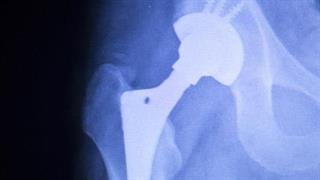

Αντικατάσταση ισχίου

Η ολική αρθροπλαστική ισχίου παρέχει άμεση κινητοποίηση, μακροχρόνια ανακούφιση από τον πόνο και μικρή πρόσθετη νοσηρότητα κατά τη χειρουργική επέμβαση.

Αρθροπλαστική ισχίου και γόνατος ηµερήσιας νοσηλείας

Η αρθροπλαστική ισχίου περιορίζει τον πόνο στη μέση